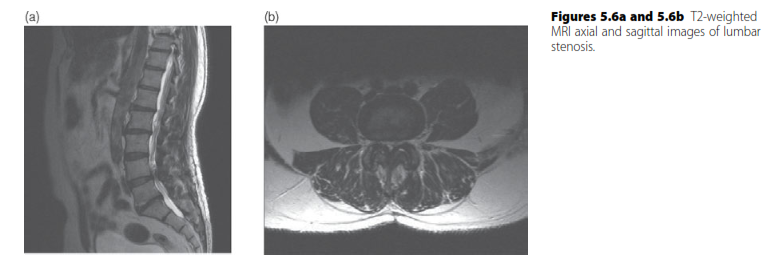

Spine structured oral questions5: Lumbar spinal stenosis and cervical myelopathy EXAMINER : A 70-year-old lad…